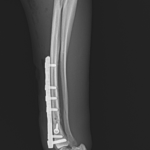

橈骨固定術 #266 6歳のワンコが落下事故により橈骨骨折をしたとの事。関節近傍から斜骨折をしています。1.5のPosition Screw、2.0 TH Plateで固定術を行いました。しばらくは安静が必要です。 症例カテゴリー 放射線治療整形外科軟部組織外科脳神経外科内科腫瘍外科救急・集中治療リハビリテーション科腫瘍内科内視鏡科脳神経科呼吸器外科中医・漢方猫の腎移植循環器科